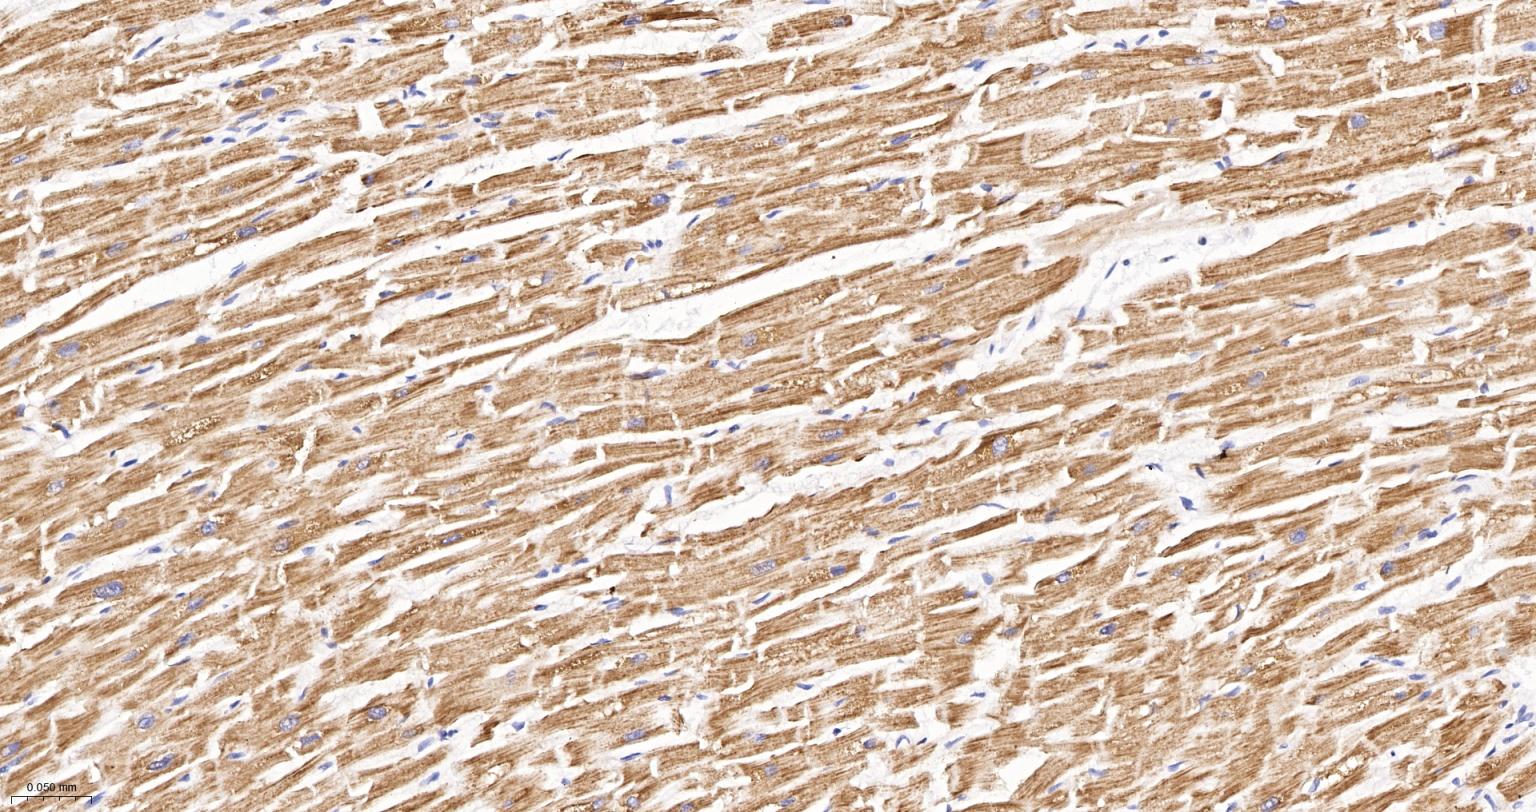

Paraformaldehyde-fixed, paraffin embedded Human Heart; Antigen retrieval by boiling in sodium citrate buffer (pH6.0) for 15 min; The section was incubated with NDUFS4 Recombinant Monoclonal Antibody, Unconjugated (bsm-62919R) at 1:200 overnight at 4°C, followed by conjugation to the bs-0295G-HRP and DAB (C-0010) staining.